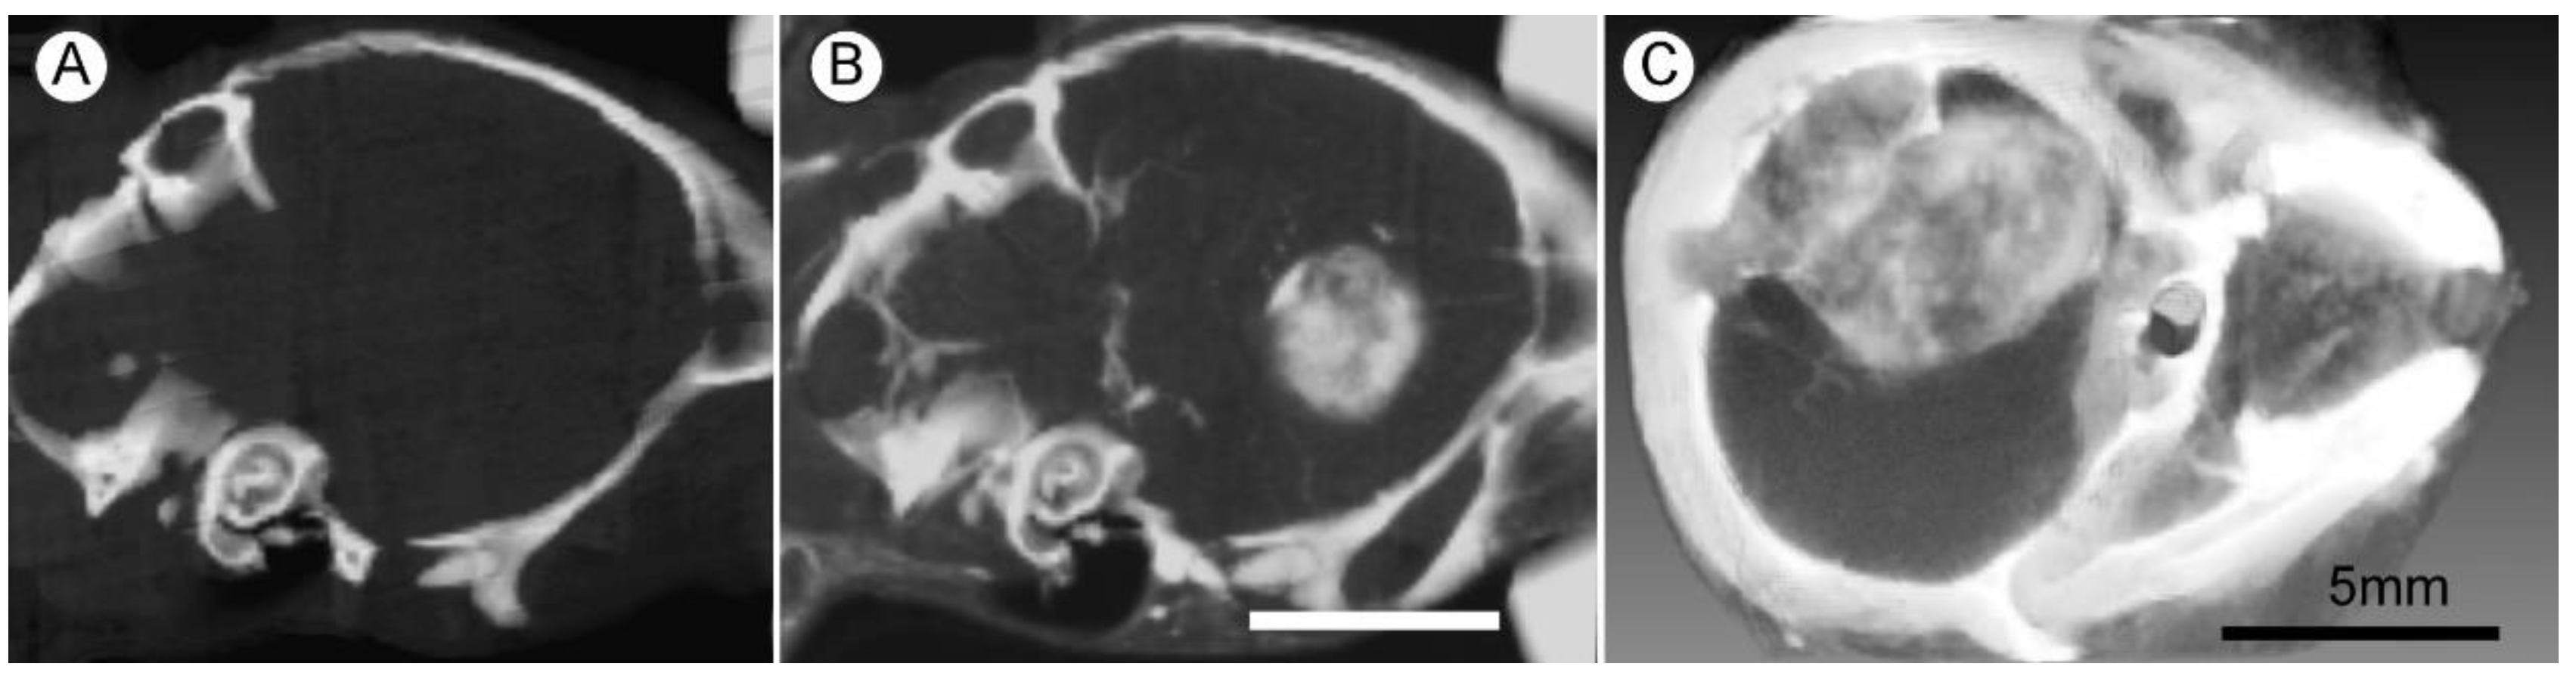

1.5. Iodine Nanoparticle Glioma Therapy